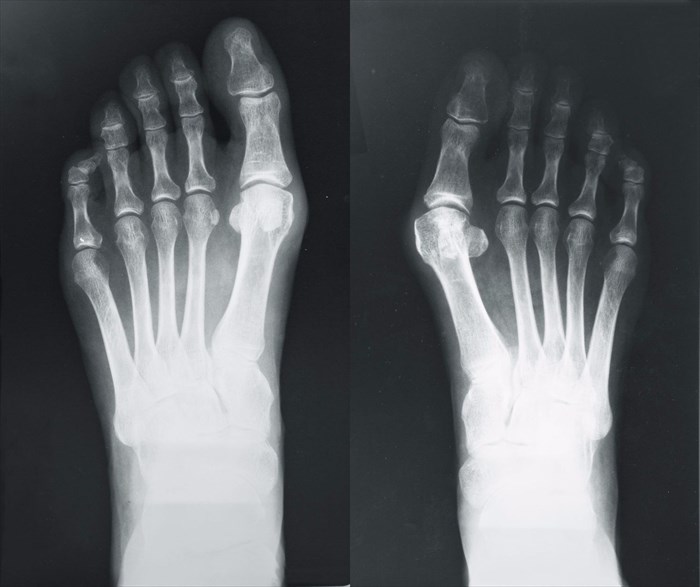

Further diagnostic analysis may be recommended should a doctor wish to determine the severity of deformity, or alternatively if an injury to the toe, joints or other structures is suspected. In this case, an X-ray may be recommended. Interpretation of radiographs (the X-ray films) can help a doctor to assess the alignment of joints in the foot, and the degree of impact the deformation is having on the foot as a whole. An X-ray will also be used as a screening mechanism for any other possible conditions that may be present, like gout or arthritis.

X-ray of a foot with valgus breach bones (bunion).

A doctor will also measure the angles between the bones in the foot (i.e. the hallux valgus angle / HVA). This is to determine the degree of the angle between the first metatarsal and the big toe (second metatarsals / or intermetatarsal angle). The development and progressive stage of a bunion will alter these angles. Normally, the upper limit of the HVA is about 15 degrees, and the intermetatarsal angle (IMA) 9 degrees. Using the information gained during an evaluation, a doctor will be able to gauge the severity of the bunion.